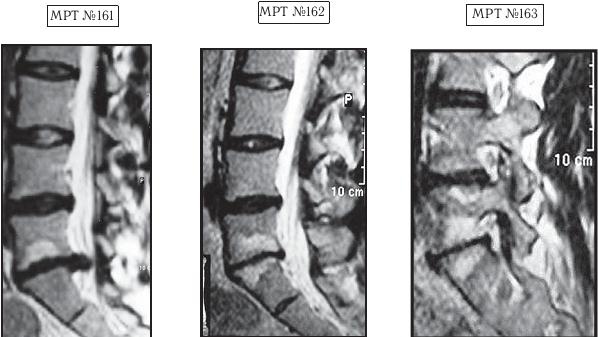

На МРТ № 161 наблюдается поясничный отдел позвоночника: секвестрированная грыжа межпозвонкового диска в сегменте LV-SI, абсолютный стеноз позвоночного канала. Светлый участок на теле позвонка LV — жировая дегенерация ткани.

На МРТ № 162 наблюдается поясничный отдел позвоночника после двух курсов лечения методом вертеброревитологии: отсутствие грыжи межпозвонкового диска в сегменте LV-SI, отсутствие стеноза позвоночного канала, стабильное состояние практически полностью утилизированного диска в сегменте LV-SI.

На МРТ № 163 наблюдается поясничный отдел позвоночника после двух курсов лечения методом вертеброревитологии: восстановление биомеханики позвоночника, нормальное соотношение дугоотростчатых суставов, фораминальные отверстия в норме.

Вот почему такие случаи считаются весьма сложными. Это практически исключает малоинвазивные хирургические методы не из-за того, что такие операции нельзя провести. Сделать их можно, только рецидив и другие осложнения — гарантированы. Наиболее разумным в таком случае, конечно, была бы тотальная дискэктомия с последующей стабилизацией с учётом биомеханических и дегенеративных изменений в вышележащих сегментах. Однако так сложилось, что данная пациентка отказалась от предложенного оперативного лечения и стала искать «обходные пути», а хирурги не стали настаивать на операции. Поэтому, спустя определённое время, она обратилась ко мне в клинику.